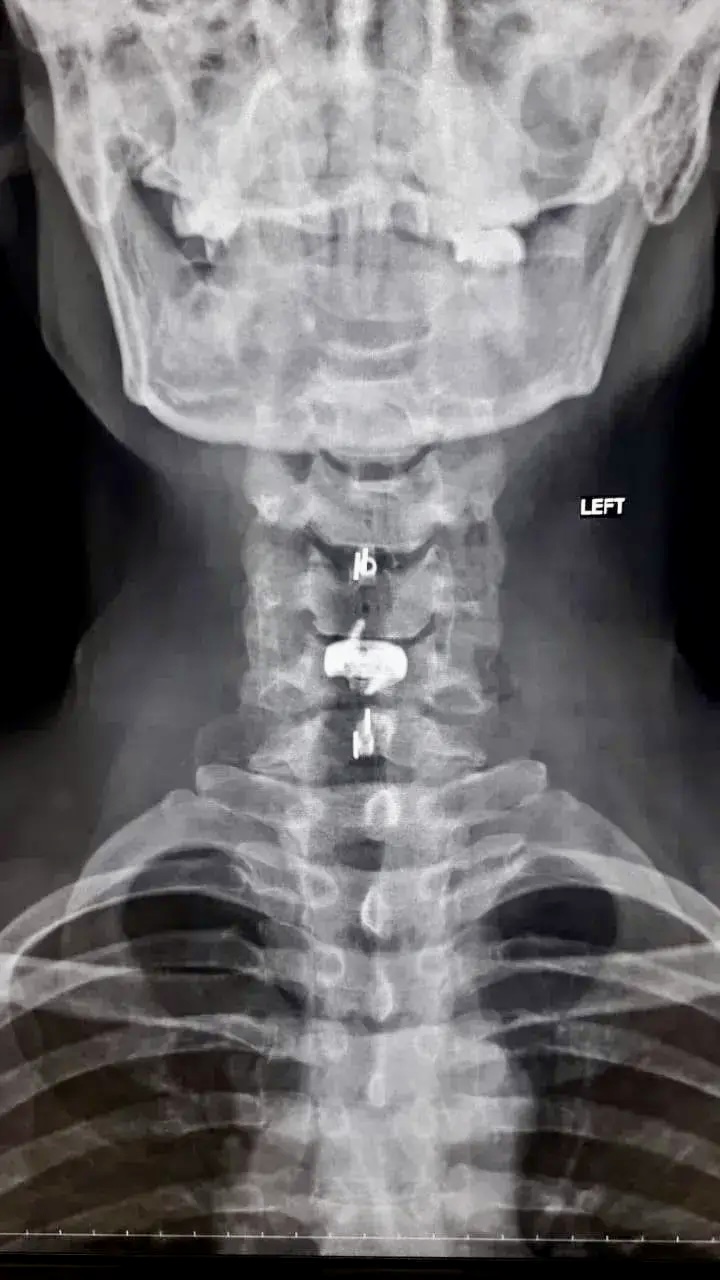

После подготовки мужчине провели операцию с применением комбинированной техники. Бригаду врачей возглавил заведующий нейрохирургическим отделением Павел Юров. Специалисты устранили сдавление и одновременно зафиксировали позвоночник, укрепив его титановыми конструкциями.